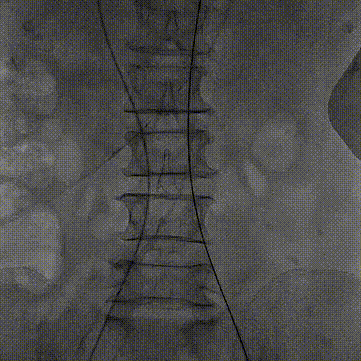

主动脉弓测量:

主动脉弓部角度稍锐,弓距稍短

•虚拟瓣环与水平面夹角60°,横位心;主动脉弓部角度稍锐,弓距偏短。